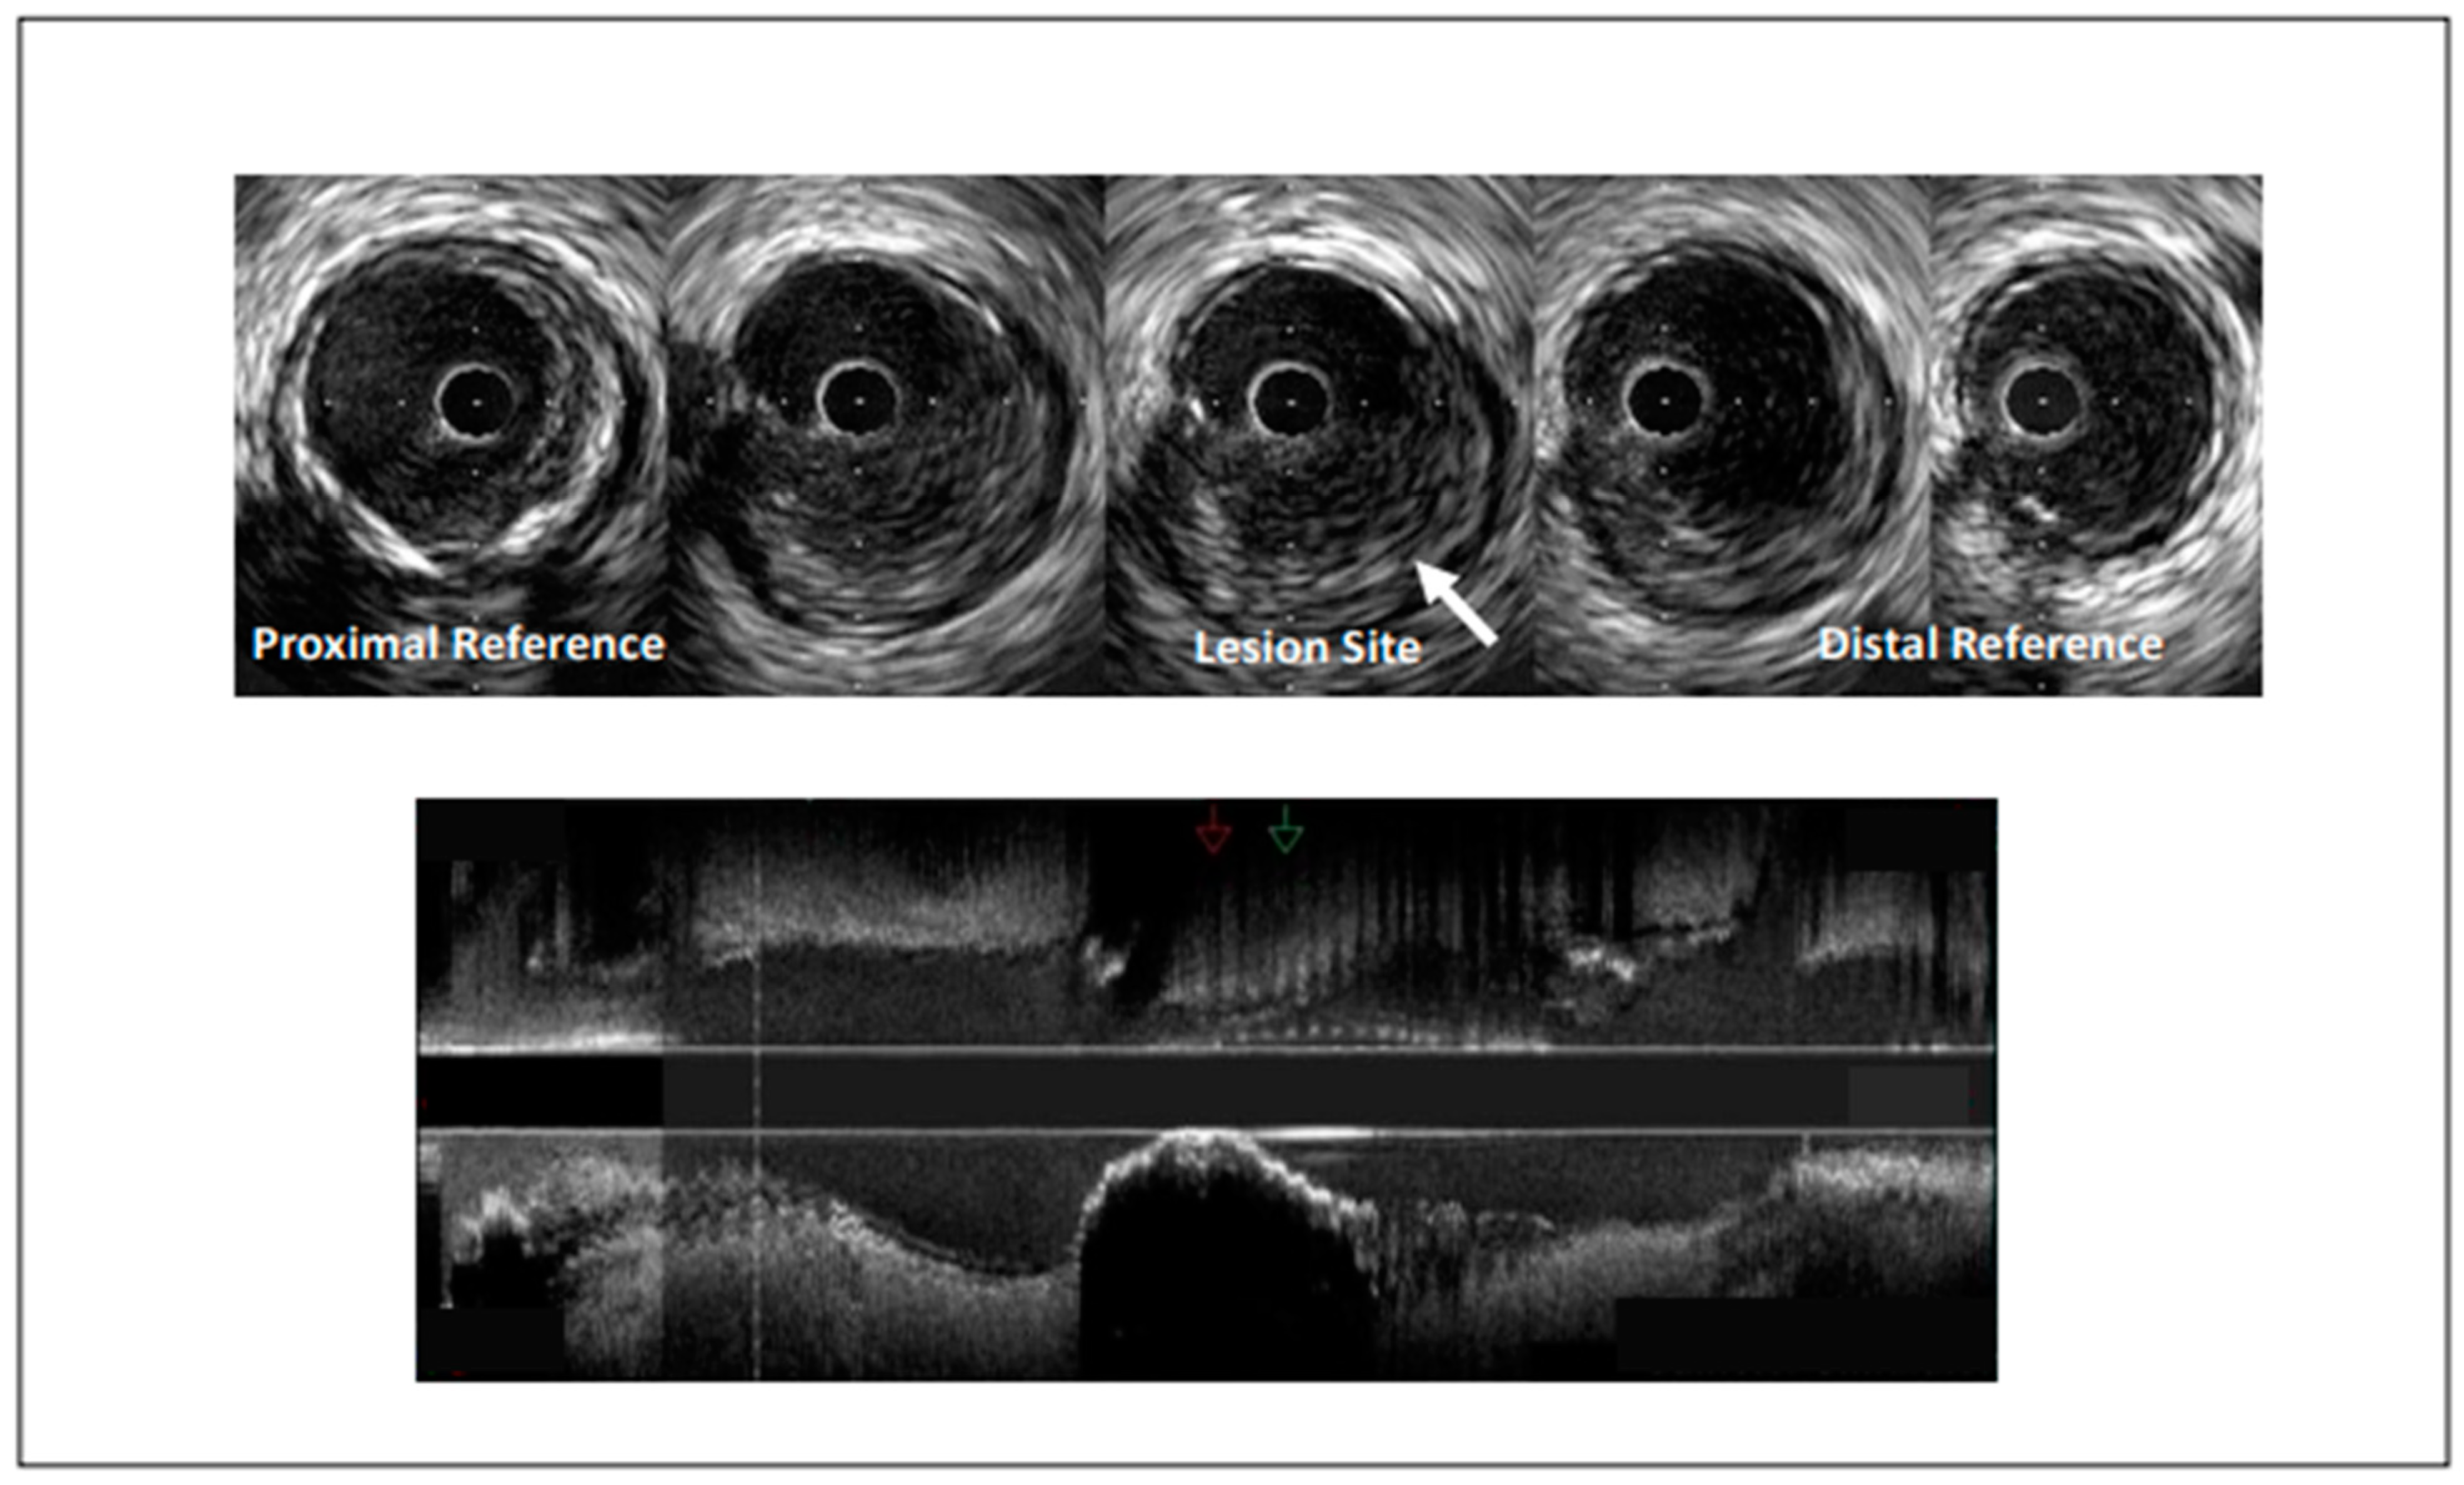

- Reynolds, H.R.; Maehara, A.; Kwong, R.Y.; Sedlak, T.; Saw, J.; Smilowitz, N.R.; Mahmud, E.; Wei, J.; Marzo, K.; Matsumura, M.; et al. Coronary Optical Coherence Tomography and Cardiac Magnetic Resonance Imaging to Determine Underlying Causes of Myocardial Infarction with Nonobstructive Coronary Arteries in Women. Circulation 2021, 143, 624–640. [Google Scholar] [CrossRef] [PubMed]